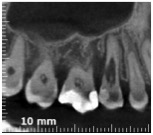

Allora per capirci qualcosa in più ho fatto una cone beam.

Riassorbimento esterno - Cone beam sagittale Riassorbimento esterno - Cone beam frontale Riassorbimento esterno - Cone beam transassiale